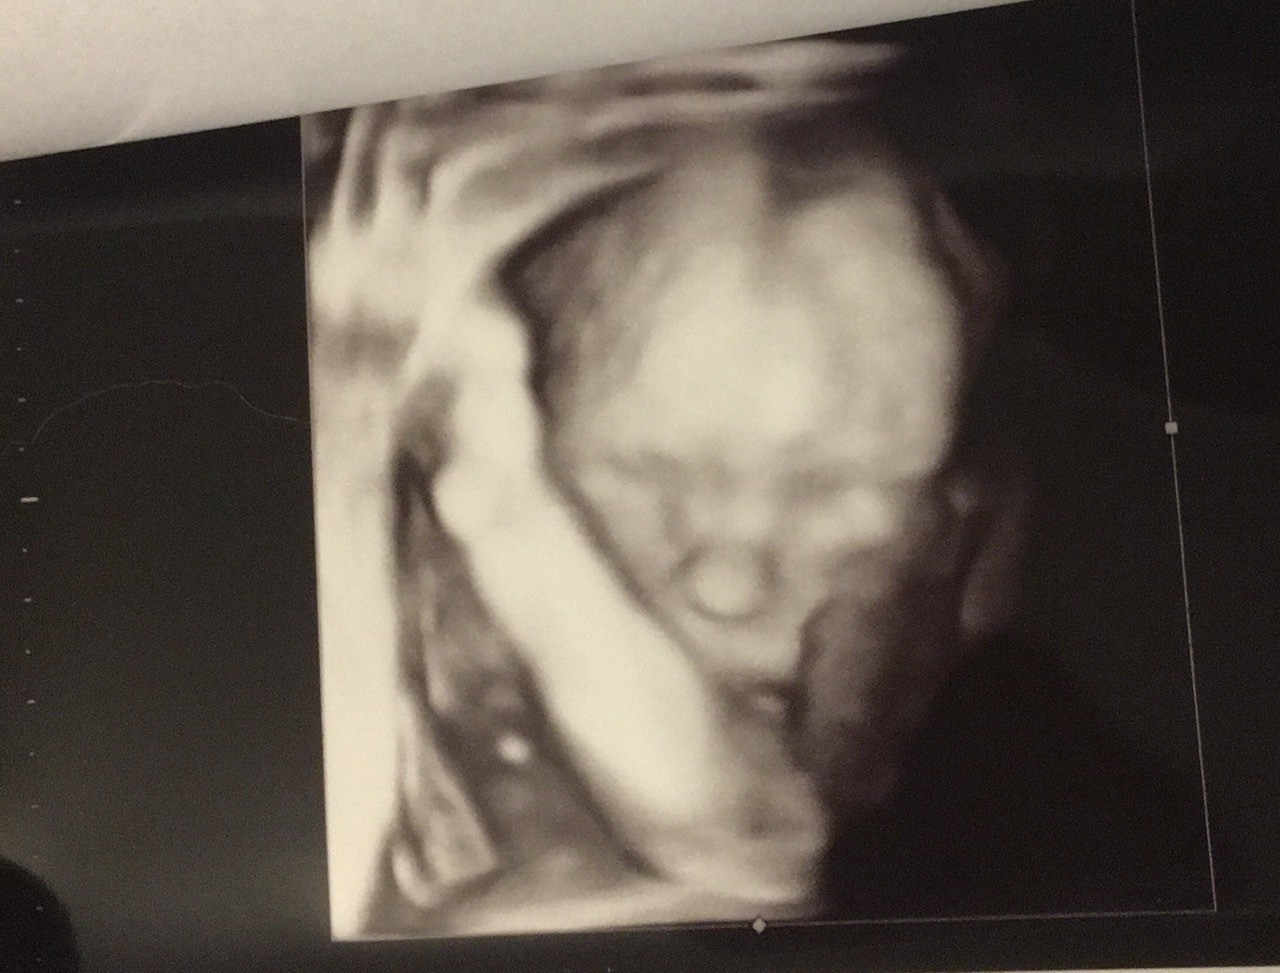

Ja takie mam, ale to z normalnej wizyty, to jakoś 20/21 tc

Załączniki

• IMG-20200721-WA0000.jpeg

IMG-20200721-WA0000.jpeg

2,3 MB · Wyświetleń: 123